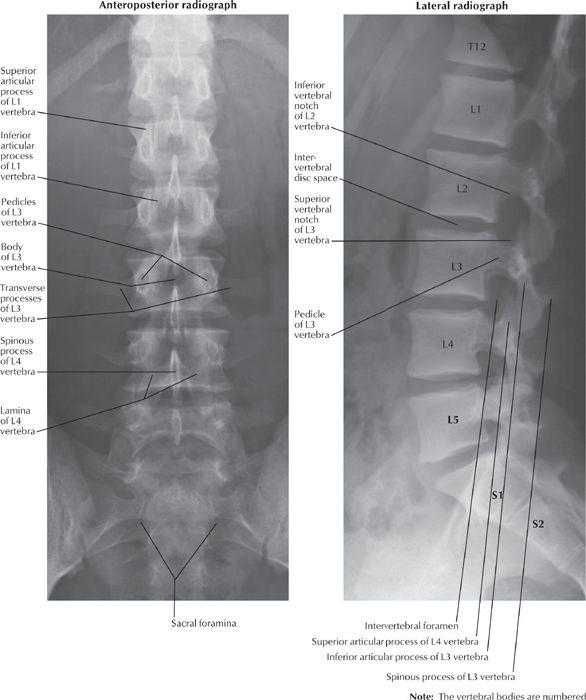

Рентген поясницы: анатомические особенности и медицинские исследования